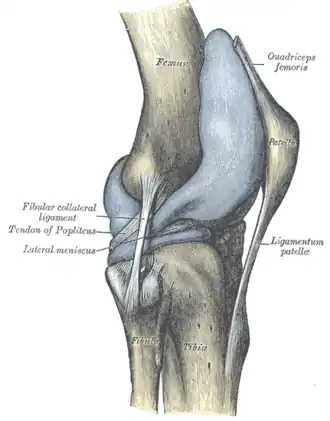

![]() Правый коленный сустав, сбоку. | |

В передней части сустава расположен надколенник (коленная чашечка). Надколенник и четырёхглавая мышца бедра соединены сухожилием, продолжением которого является связка надколенника. В связочный аппарат входят:

- боковые (малоберцовая и большеберцовая коллатеральные)

- задние (подколенная, дугообразная, связка надколенника, медиальная и латеральная поддерживающие)

- внутрисуставные (крестообразные, поперечная связка колена (между менисками)